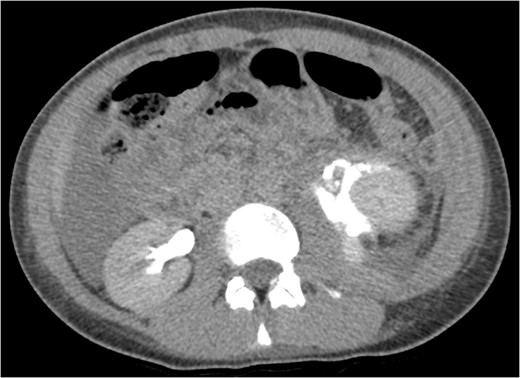

CT IVU- confirmed extravasation of contrast medium around the left kidney and ureter, the rupture being at the level of the PUJ.